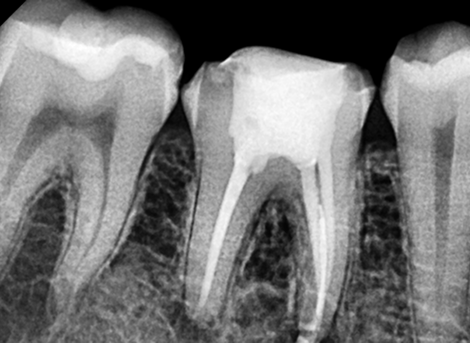

Complete disinfection of the root canal.

Laser Cleaning

Sealing the Canal